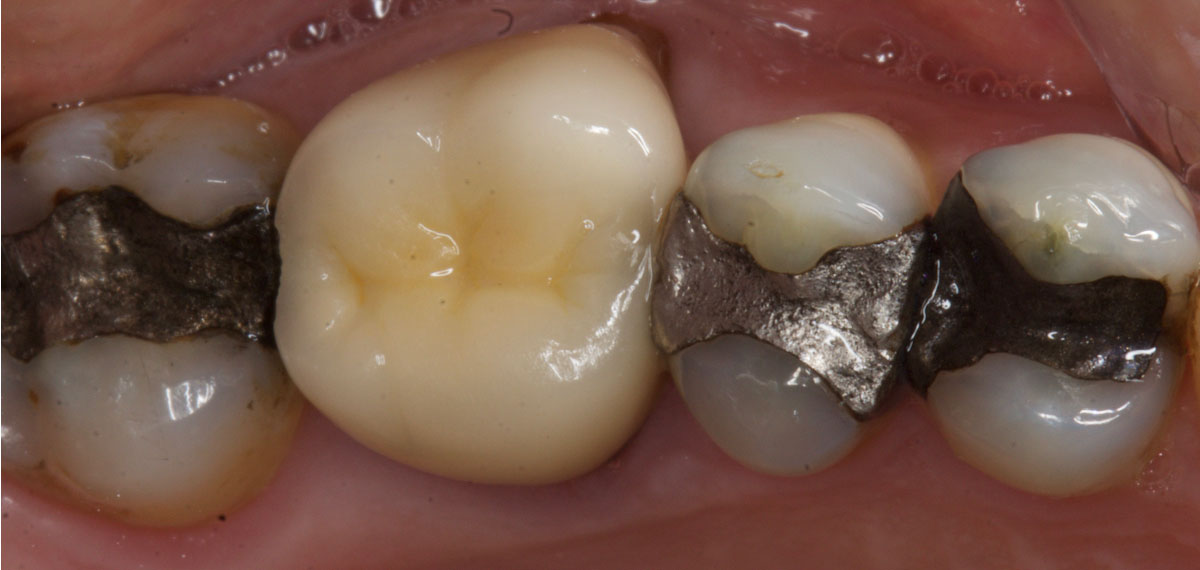

A heavily restored posterior dentition, with a history of fractures, may benefit from converting to canine guidance. This will also limit lateral forces on the weakened posterior teeth.

Patients in both of the photos below have heavily restored posterior dentitions. You could also make an argument that several cuspal coverage restorations are indicated.

However, if the patient did not consent to this, but wished to limit the risk of future fractures, then restoring the canines and ensuring canine guidance (for instance by canine rises in composite) would do this.